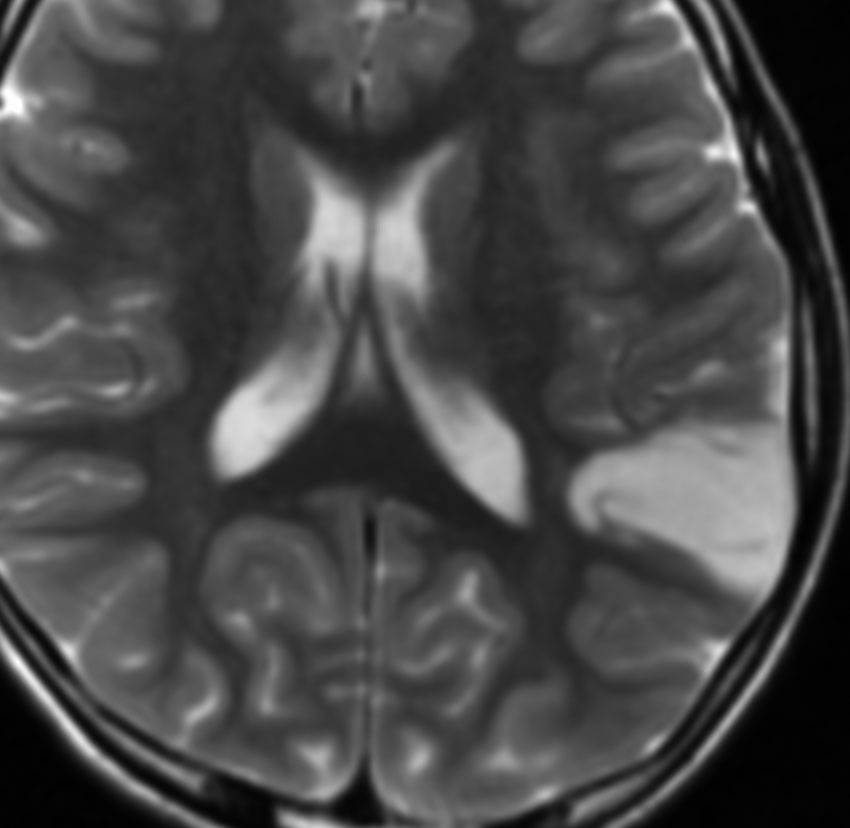

10歳でてんかん発症して難治性になった例